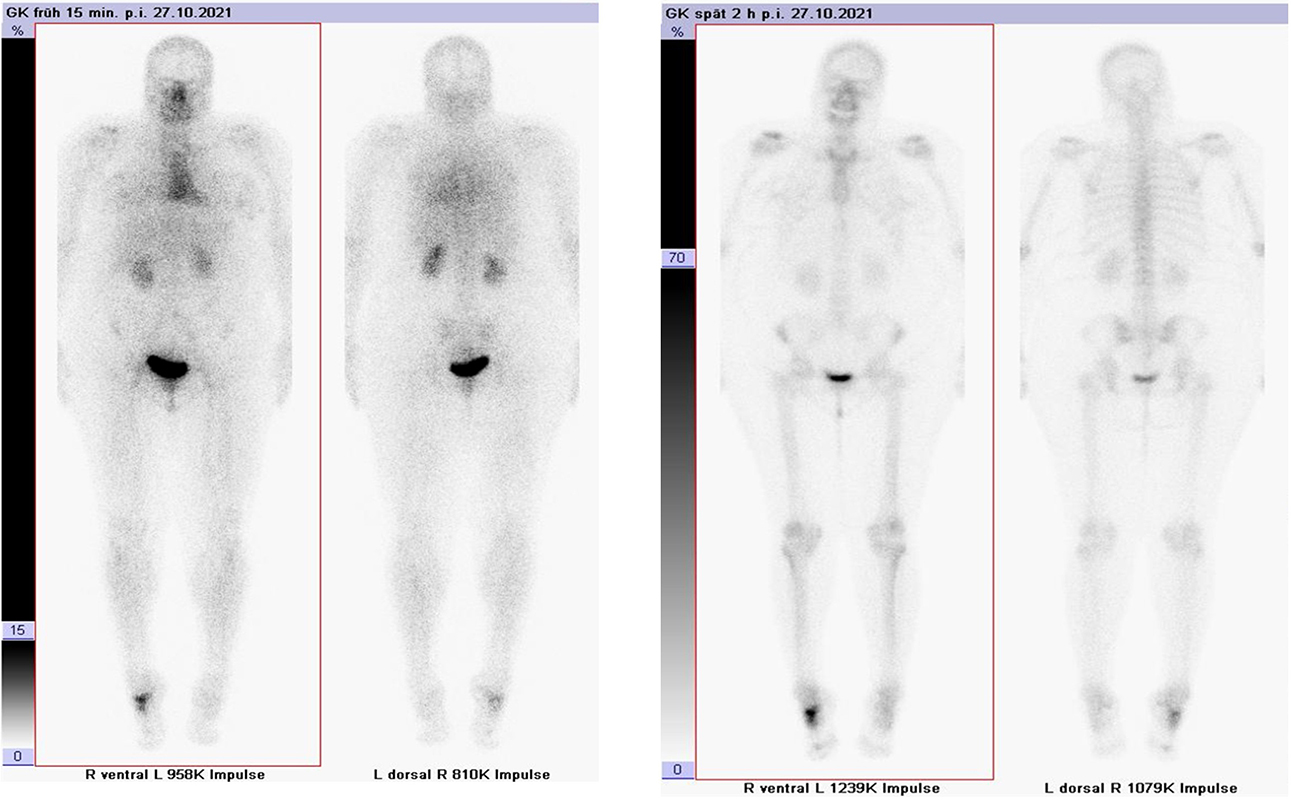

Abbildung 1.8.a und b: Akute Arthritis bei bekannter Gicht in beiden OSG: links die Früh-/Weichteilphase; rechts die Mineralisations­phase. Deutliche, entzündlich bedingte Mehranreicherungen in der Früh-/Weichteilphase. In der Mineralisation­sphase erkennt man die entzündliche Mitreaktion der subchondralen Gelenkabschnitte.

Zum Lesen der Bildbeschreibung und zur Vollansicht bitte das Bild anklicken. Bild: H. C. Rischke

Abbildung 1.8.c - e: Akute Arthritis in beiden OSG, rechts > links. Im SPECT/CT erkennt man die Mitreaktion der subchondralen Gelenkabschnitte. Die Arthritis ist so akut, dass (noch) keine ossären morphologischen Veränderungen im CT abgrenzbar sind.

Zum Lesen der Bildbeschreibung und zur Vollansicht bitte die Bilder anklicken. Bilder: H. C. Rischke